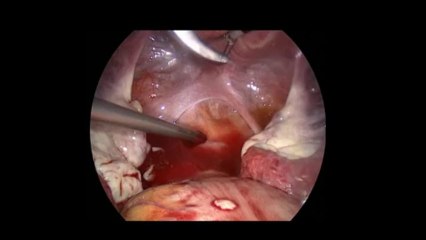

Laparoskopi ile Endometiroma (Çikolata kisti) operasyonu 1 - Prof. Dr. Aydan Biri

Laparoskopi ile Endometiroma (Çikolata kisti) operasyonu 1 - Prof. Dr.